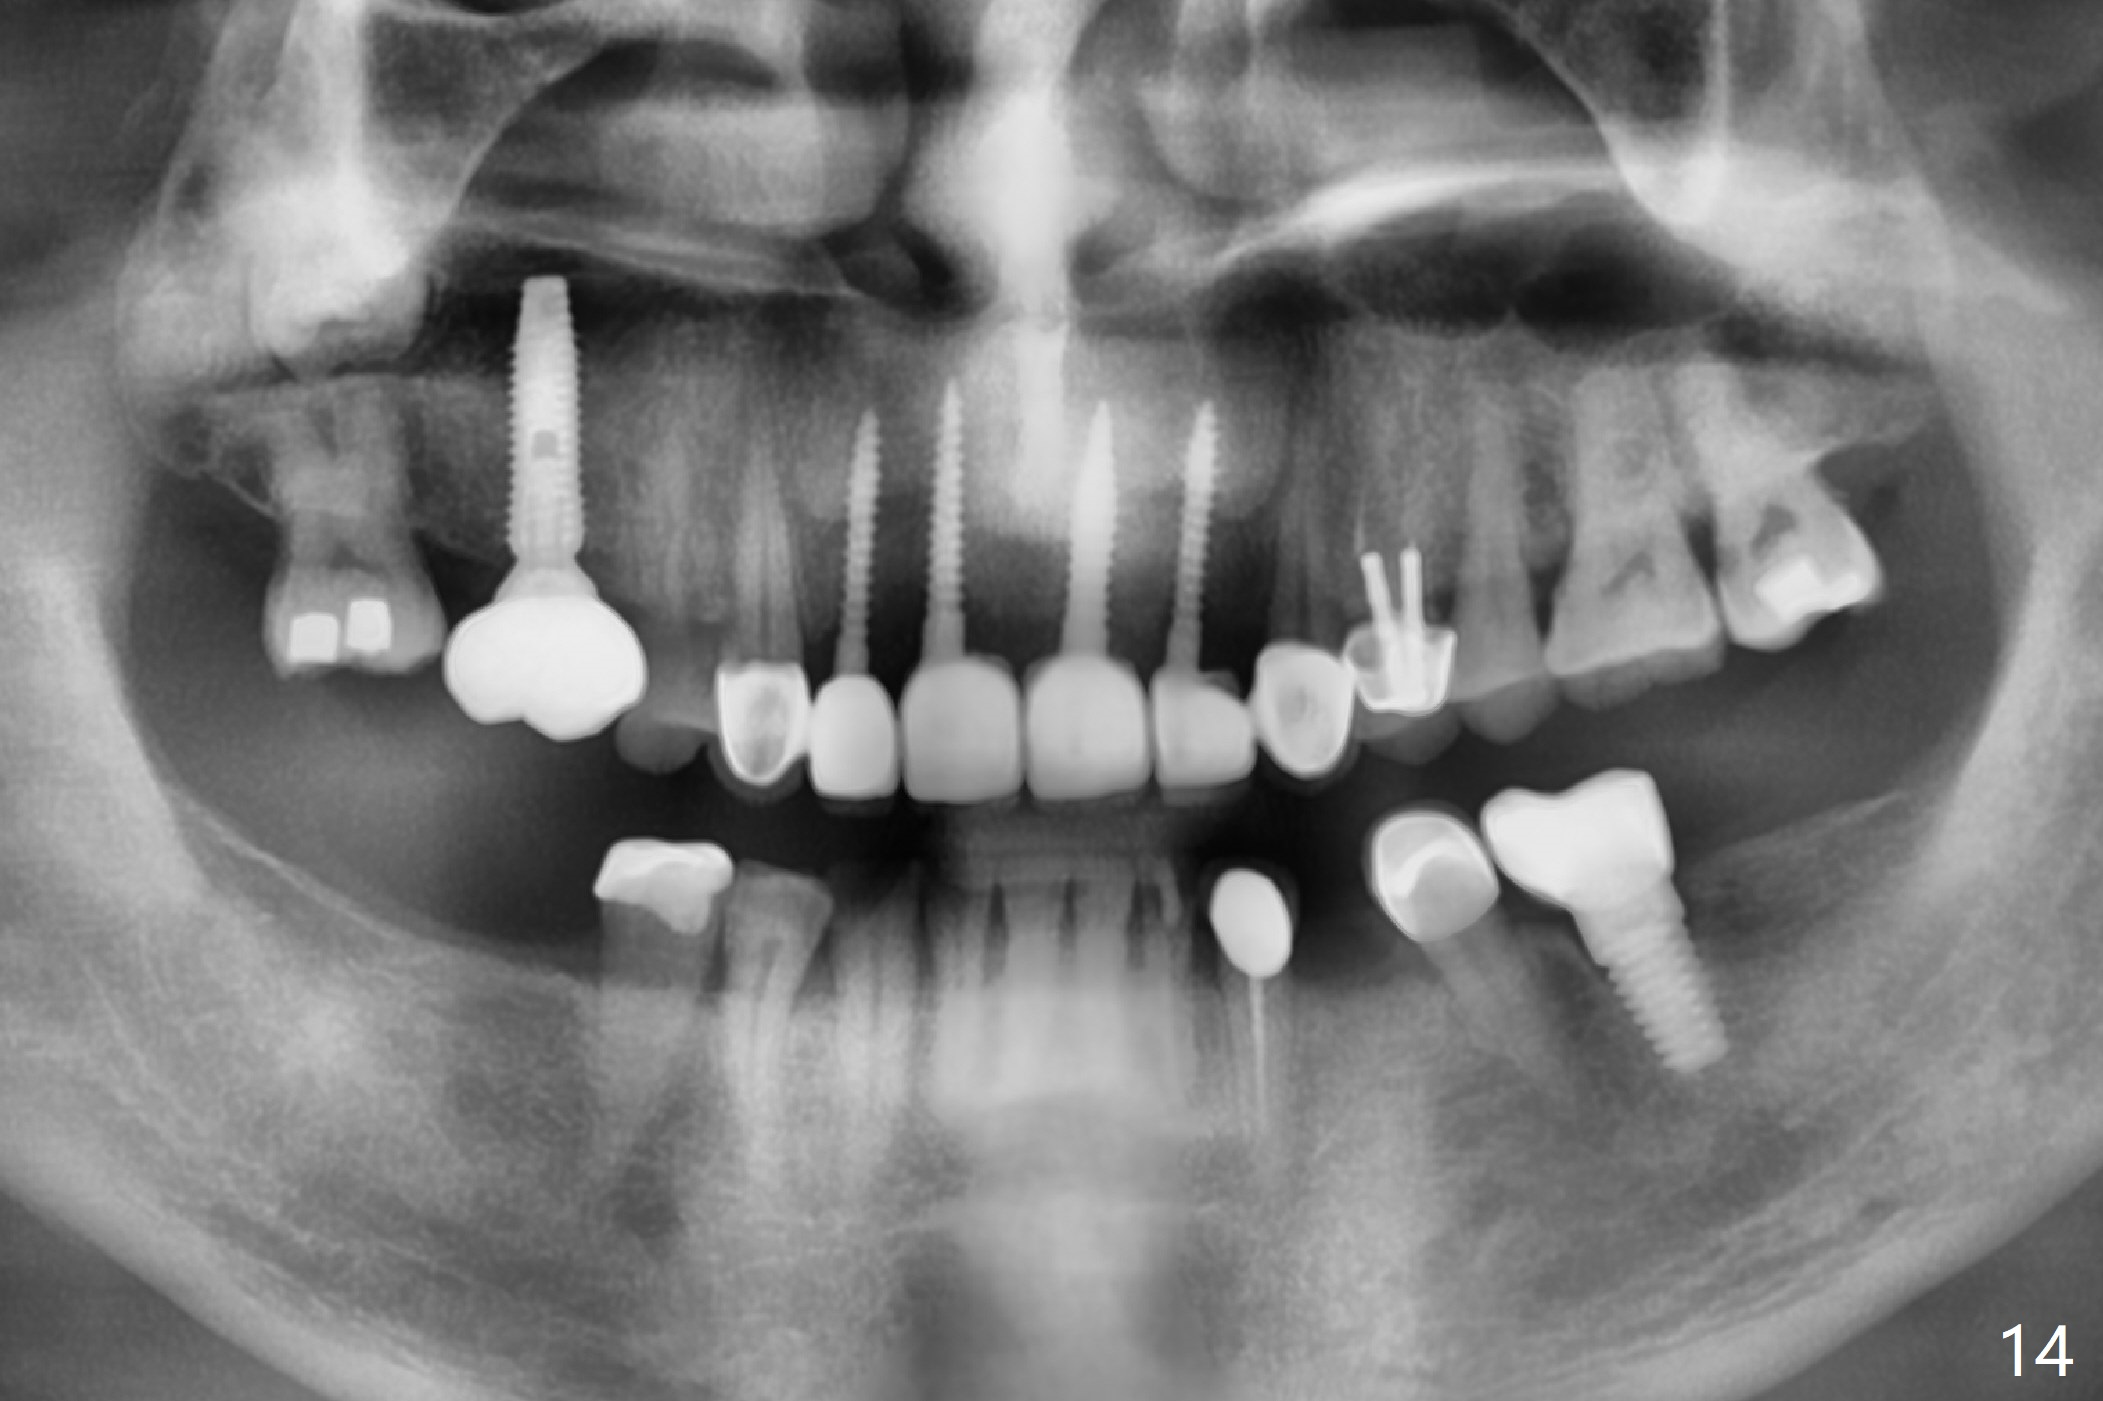

The palatal cusp of the affected 2nd premolar is apparently rotated distal (Fig.1). It is more obvious for the socket (Fig.2): the palatal (P) portion of the socket is more distal than the buccal (B) one. When the gauze is removed (Fig.3), Lindamann bur is used to remove the disto(D)palatal bone of the socket (data not shown), followed by starter drill in the DP wall obliquely (Fig.3'). Once the drill enters the bone for 1-2 mm, the bur is straightened and pushed slightly distal (Fig.3''). Fig.4 shows a parallel pin distal (overcorrect) to the original socket (Fig.4 red dashed line). Sequential osteotomy is conducted until 3.8x13 mm drill for 18 mm (Fig.5): note the 2 steps of the osteotomy (red lines). Since the apical portion of the osteotomy is larger than the drill, a larger implant than expected (5x16 mm) is placed. The implant ends up in the middle of the edentulous area (due to the stepped osteotomy; Fig.6-9; >60 Ncm). Vera allograft is placed (Fig.7-9 *) prior to and after placement of a 6.5x4(3) mm abutment (Fig.8-10). The remaining socket opening is sealed with a piece of Collagen plug (Fig.10 *). The socket is then closed by an immediate provisional (Fig.11 P). The abutment is retightened 2 months postop (Fig.12,13). The crown is cemented 4.5 months postop. Panoramic X-ray and CT are taken nearly 7 months post cementation (Fig.14,15) when the patient is ready for #30 implant guide preparation.